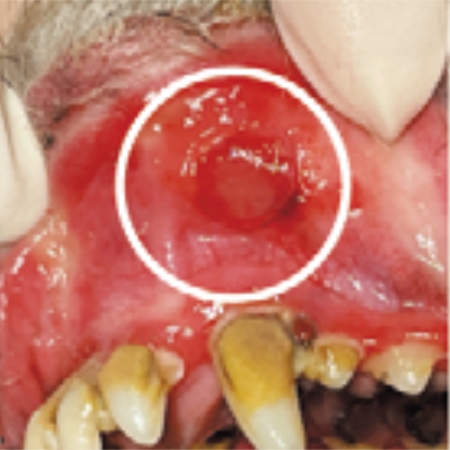

人と同じように、犬にも口内炎ができます。口の中の粘膜が炎症を起こし、赤くなったり、ただれたりするほか、出血したりします。犬では、進行した歯周病に続発して起きることが多いとされています。

口の中にあらわれる症状